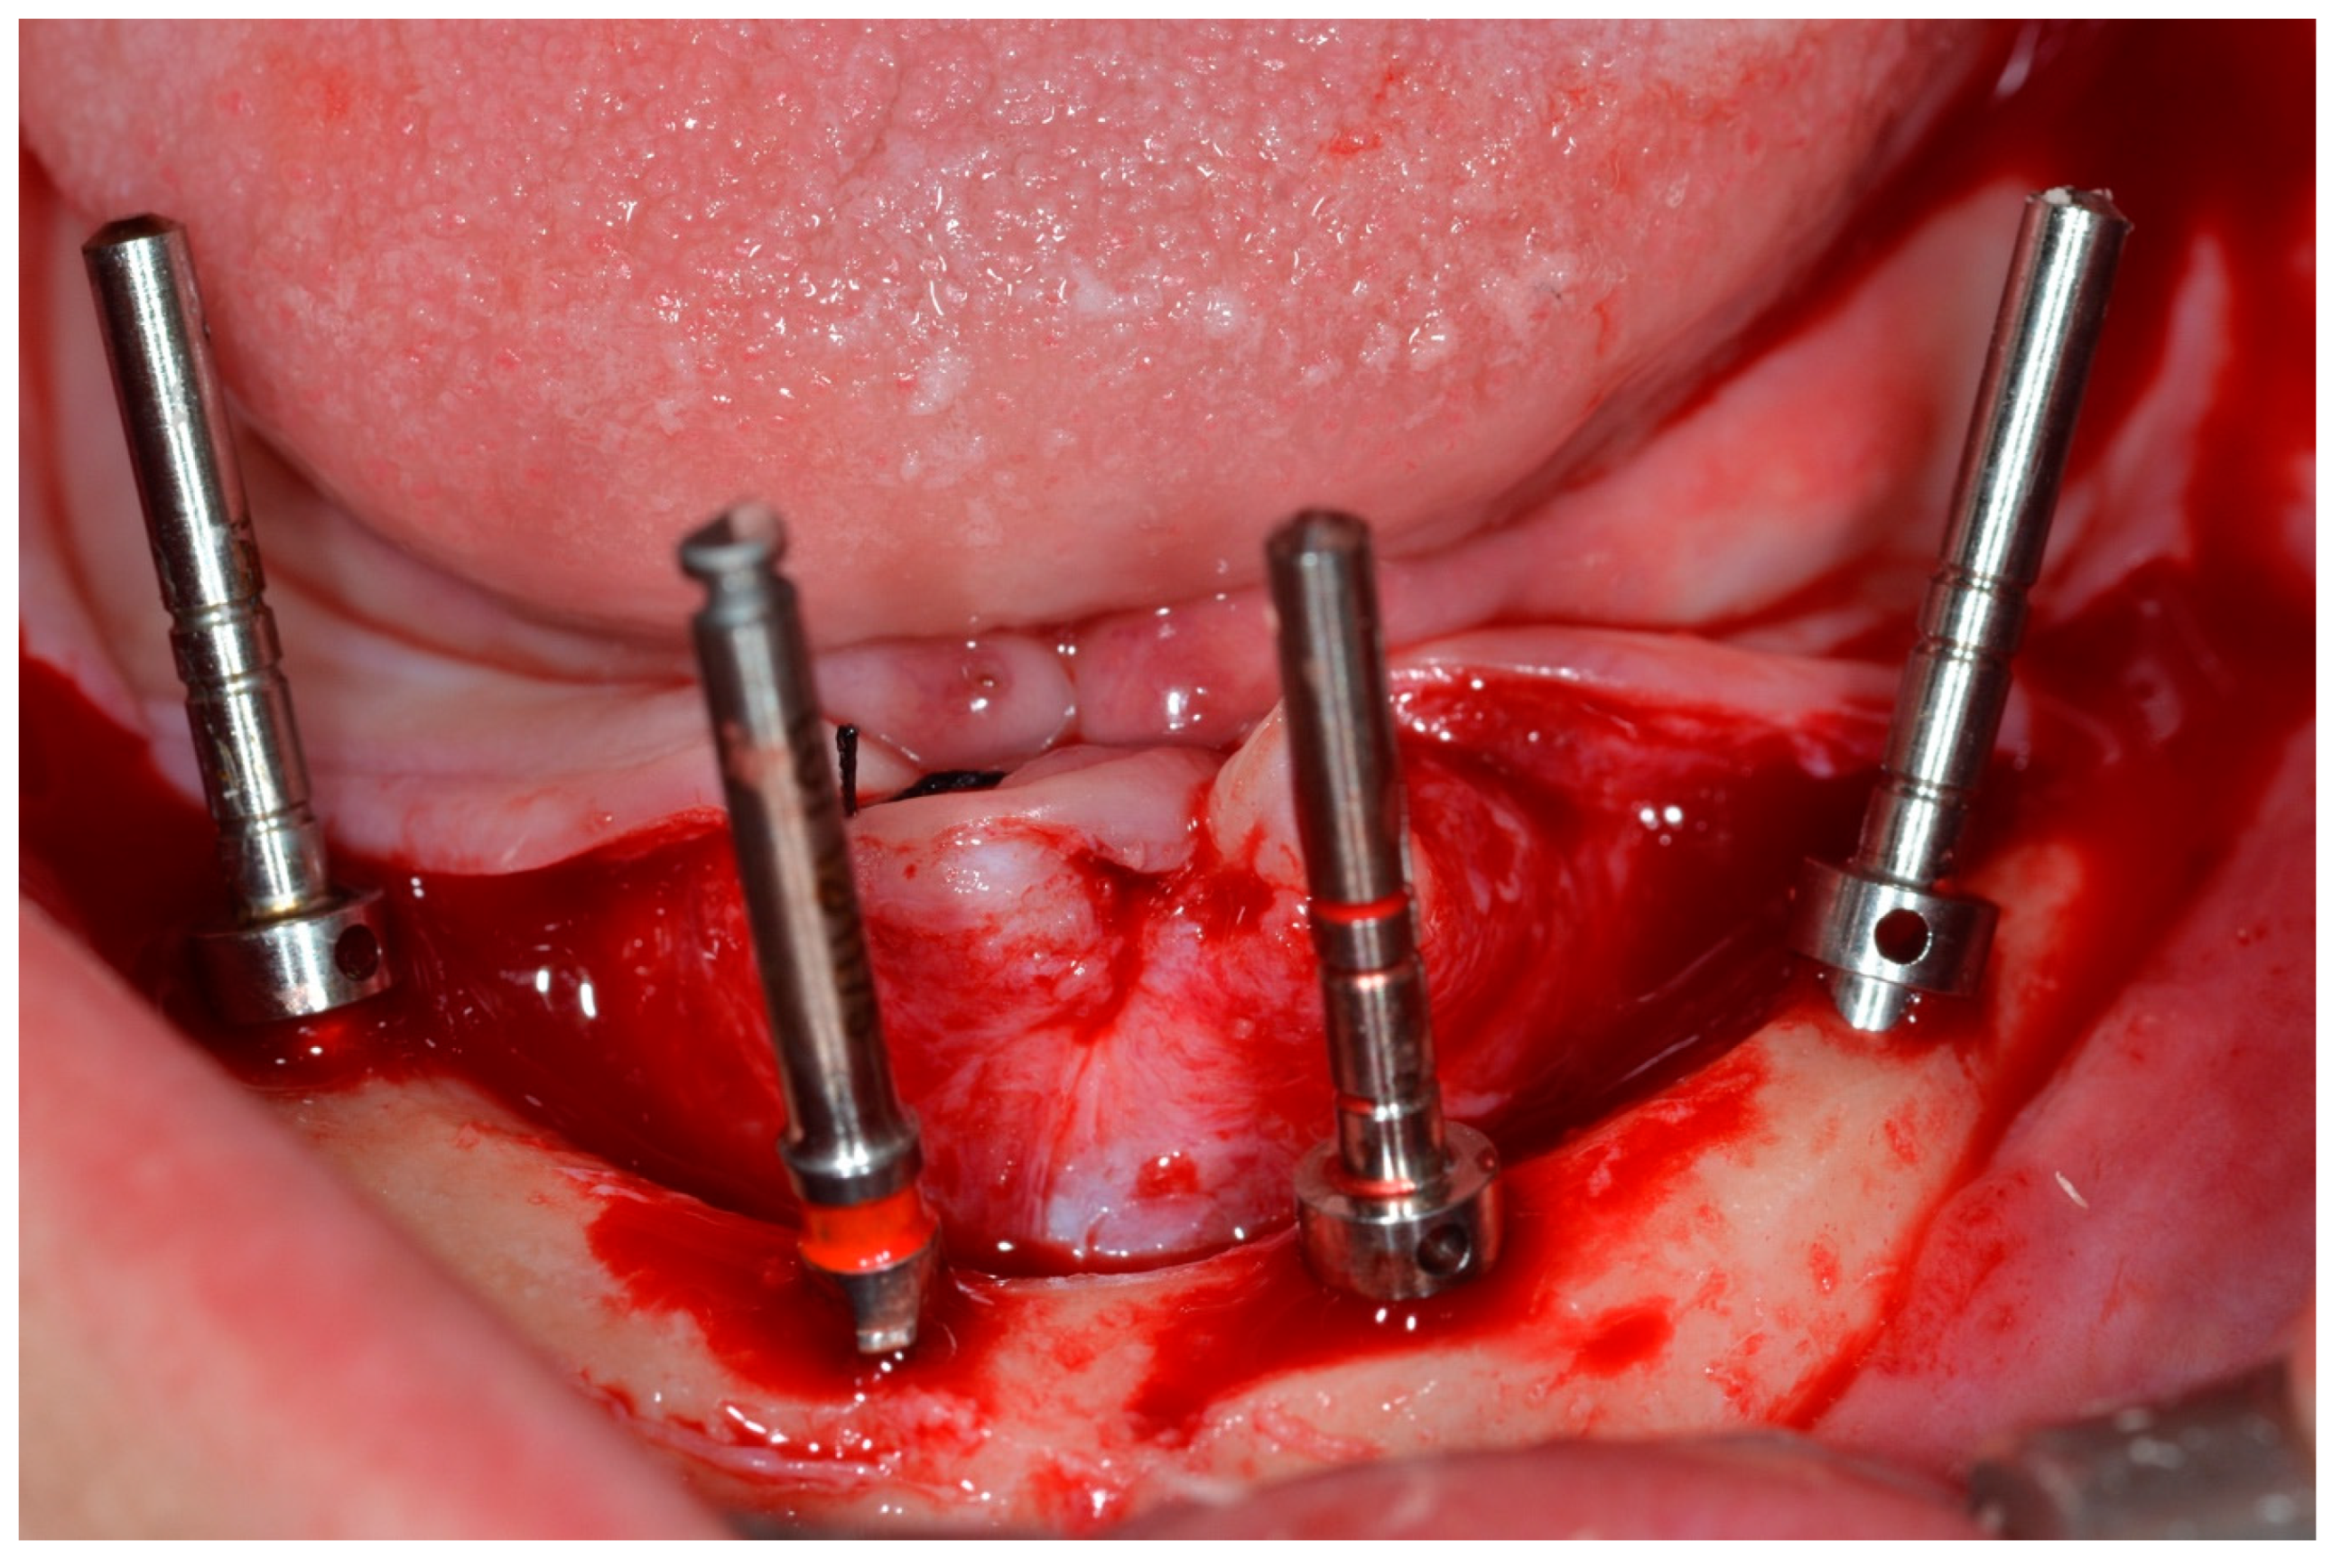

The drilling sequence for implant installation was performed according to the instructions of the implant manufacturer (Dérig, São Paulo, SP, Brazil), according to the All-on-Four protocol (Figure 4) [19,20,21].

Figure 4.

View of the mandible with parallel pins to check implant positions for the All-on-Four concept.

During bone instrumentation, when the surgeon’s experience enabled them to sense that the implant sites would have poor bone density, they performed sub-instrumentation to obtain the highest torque value possible at every site [10]. The surgeons decided this based on their extensive experience with All-on-Four treatments to promote lateral compression of the bone, thereby increasing primary stability [10]. The implants used in this study were tapered, with a rough surface, internal tri-channel connection implants (TRI Bioneck RP ∅ 4.3 mm, Dérig, São Paulo, Brazil) (Figure 5).